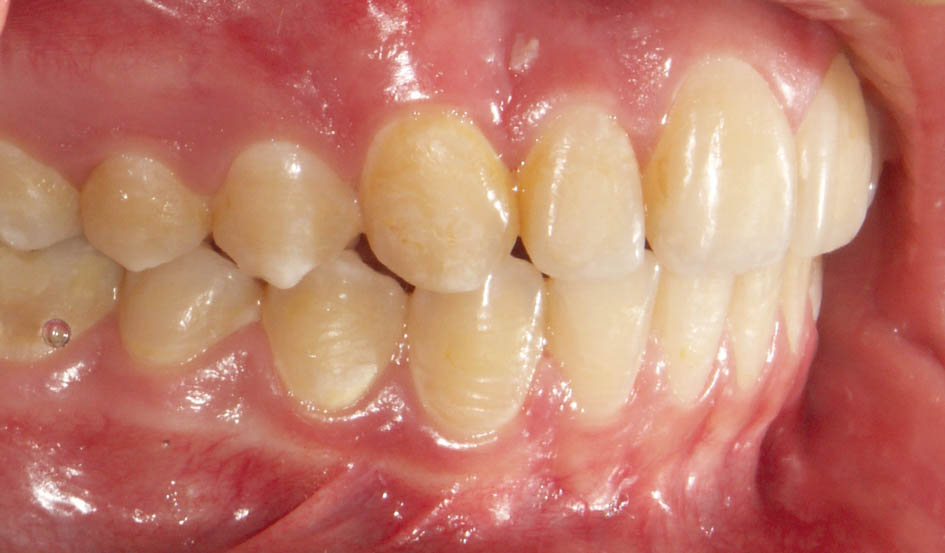

درشکل78-5 و79-5 رابطه مولری یک کاسپ کامل کلاسII است و بعد از پروترود شدن قدامیهای بالا به کمک براکتها (شکل80-5) مندیبل هم حدود 3mm جلوتر قرار گرفته است.

در بیماران دیپبایت کلاسII جابجایی خلفی مندیبل خوب است چون با پروترود شدن قدامیها (تبدیل بیمار Div2 به Div1) مشکل کلاسII بیمار کمتر میشود و درمان فانکشنال زودتر تمام میشود. بعد از Div1 شدن پلاک فانکشنال بدهید و در یک دوره کمتر از 9 ماه شاهد کلاسI شدن بیمار (شکل81-5) میشوید.

شکل 78-5: بیمار یک کاسپ کامل کلاسII و دیپ بایت شدید است.

شکل 79-5: نمای روبرو کمبود اورجت را نشان میدهد.

شکل 80-5: پروترودشدن قدامیهای بالا باعث حذف فشار دیستاله روی مندیبل گشته و مندیبل جلوتر قرار میگیرد.

شکل 81-5: کلاسI شدن بیمار شکل 78-5 با پلاک فانکشنال آندرسن